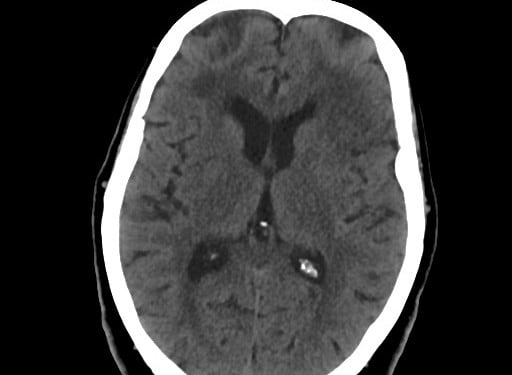

Ottawa Subaraknoid Kanama Kuralını oluşturan risk faktörleri

- Yaş ≥ 40

- Boyun da ağrı veya sertlik

- Tanıklı bilinç kaybı

- Efor sırasında başlaması

- “Thunderclap başağrısı” (anında şimşek çakar gibi baş ağrısı)

- Muayenede boyun fleksiyonununda sınırlama (çeneyi göğüse dokunduramama veya başını 3 cm kaldırmama olarak tanımlanır)

Bu risk faktörleri, spontan subaraknoid kanama için yüksek risk altında olmayan hasta popülasyonlarının sınırlarını belirler ve daha fazla tetkik gerektirmeyen hasta popülasyonunu ayırt etmeyi sağlar. subaraknoid kanama tanılı hastalar acil servise ilk başvuruda % 5.4 hasta yanlış tanı konulur.